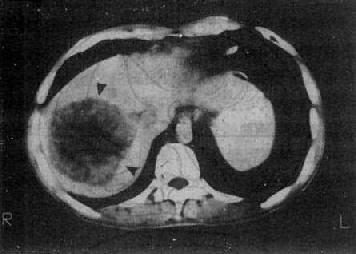

图4-3-7 肝血管瘤

CT增强扫描,注射造影剂后10分钟,可见原来两个低密度

区被造影剂基本完全充盈(↓)。图为两个相邻层面